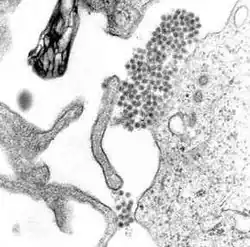

| Denguevirus | |

| Familie | Flaviviridae |

| Slægt | Flavivirus |